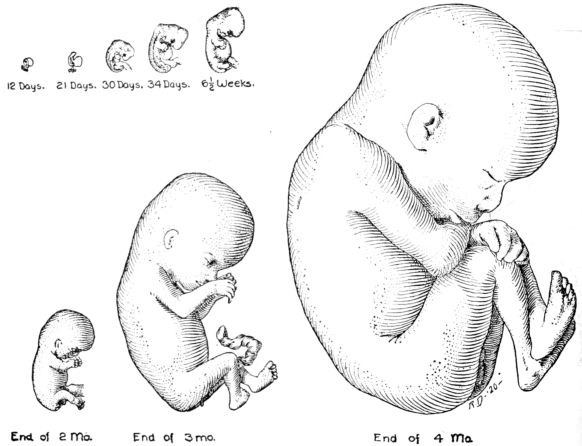

| 26. | Outlines of fetus at different stages | 78 |